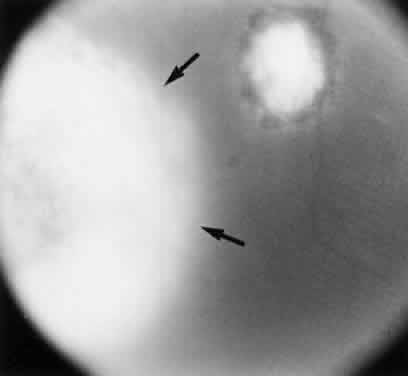

Similar, well-documented cases of retinochoroiditis caused by Toxoplasma after acquired systemic toxoplasmosis have been reported.27,26,51–54 In an outbreak of systemic toxoplasmosis that occurred in October 1977 in Atlanta, Georgia, 37 patients became ill or had serologic evidence of acute infection.22 Epidemiologic studies suggest that infected cats in the riding stable were the source of the infection. Aerosolization of oocysts and hand-to-mouth contact were the presumptive means of transmission. All patients were examined and followed for a year without evidence of Toxoplasma retinochoroiditis. In a 4-year follow-up study, only one patient had shown evidence of ocular disease consisting of an acute retinochoroiditis.27 This suggests that many sporadic cases of acute retinochoroiditis result from or may follow an episode of acquired toxoplasmosis (Fig. 6). Notice that not all cases of retinochoroiditis occur simultaneously with an episode of acquired systemic illness but may manifest any time after the onset of the disease, from a few weeks to years after the acute episode of acquired systemic toxoplasmosis.27 The case described in Figure 6 is one such example.

Fig. 6. Toxoplasma retinochoroiditis after acute systemic toxoplasmosis. A 36-year-old man presented with history of seeing floaters in the right eye of 1 week's duration. The onset of his ocular symptoms occurred 56 days after a flulike illness with postauricular lymphadenopathy. Acute and convalescent serum specimens were obtained and showed an increase in Toxoplasma antibody titers from negative to 1:1024. A. Single focus of retinochoroiditis below the macular area of the right eye (vision: 20/200 [metric equivalent 6/60]). The left eye was normal with 20/20 (6/6) vision. B. Fluorescein angiography (early late phase) indicates leakage from retinal capillaries. C. Two months after a 3-week course of clindamycin, sulfadiazine, and systemic corticosteroids, the lesion completely resolved. The patient's vision decreased because of epiretinal gliotic membrane formation, causing macular pucker and subretinal neovascularization.